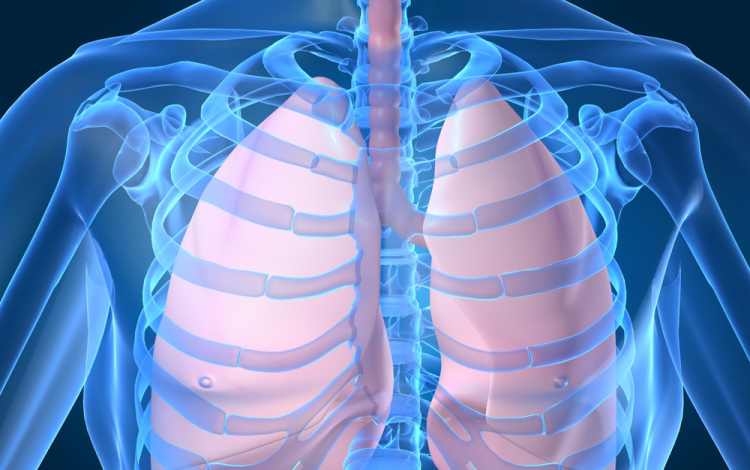

Húszan várnak tüdőátültetésre Magyarországon

Húszan várnak tüdő-transzplantációra az országban, tavaly 12 magyar betegen hajtottak végre ilyen szervátültetést külföldön

- mondta Kásler Miklós, az Országos Onkológiai Intézet főigazgatója vasárnap az M1 aktuális csatorna esti műsorában. A főigazgató ezt azzal kapcsolatban közölte, hogy még idén elvégezhetik az első tüdőátültetést Magyarországon.

Magyarországról tavaly 37 tüdőt szállítottak Bécsbe átültetési céllal; ha nálunk is elérhetővé válik a műtét, akkor várhatóan a környező országokból is Budapestre érkezik majd a betegek egy része Bécs helyett - mondta a főigazgató.